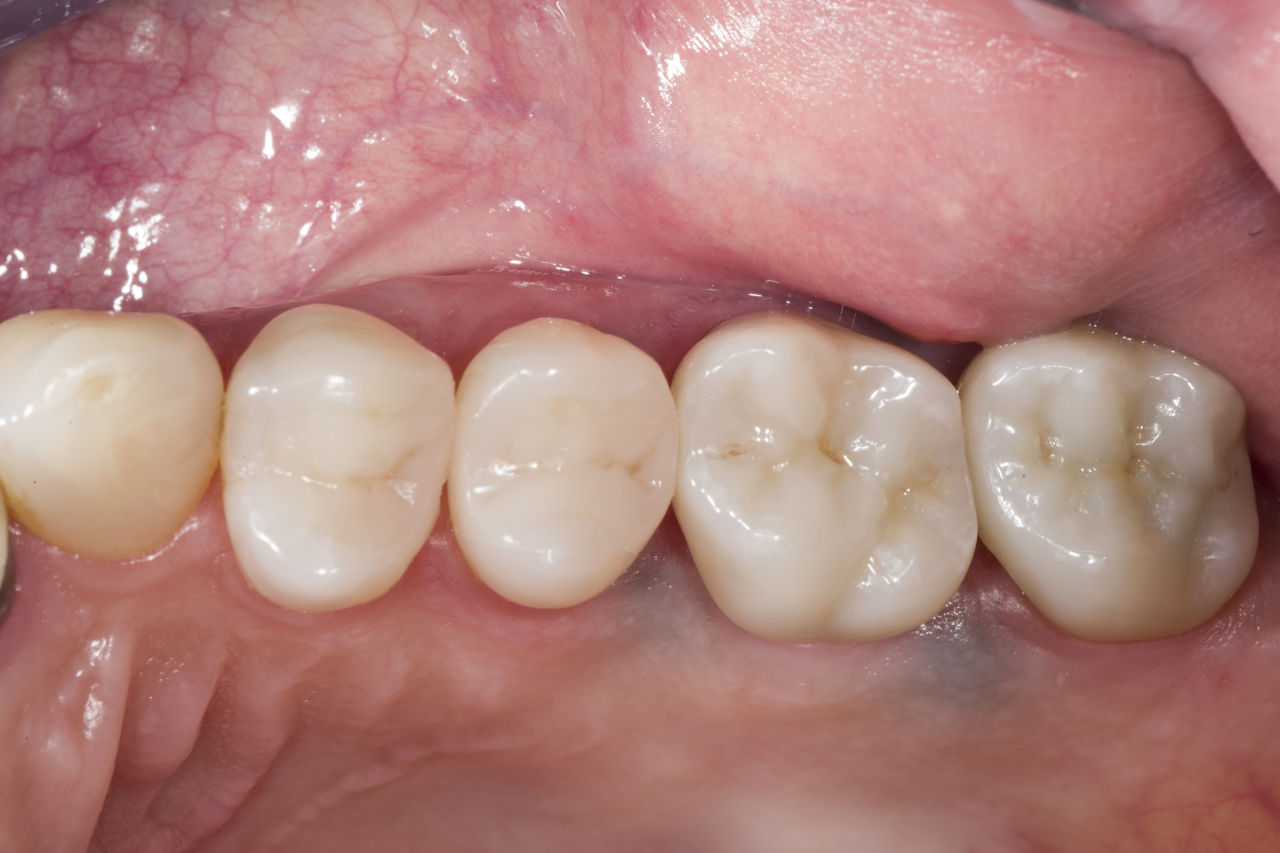

Lower second molar chairside restoration

A partial CEREC Tessera crown

A lower second molar with sensitivity presented with cracks as well as an extensive Class I composite restoration on the buccal surface. According to the minimally invasive concept a CAD/CAM partial crown was planned, fabricated and bonded using CEREC Tessera in a single visit.

Before: Failed amalgam restoration needing replacement. Patient complaining of sensitivity and tooth presenting multiple cracks.

After: Chairside CAD/CAM partial crown restoration fabricated with CEREC Tessera Advanced Lithium-Disilicate glass ceramic.

Dr. Carlos Eduardo Sabrosa

Rio de Janeiro, Brasil